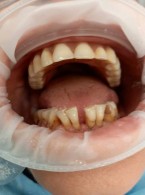

SPECJALISTA RADZI: Pacjent z anoreksją

Do mojego gabinetu zgłosiła się 29-letnia kobieta ze zmianami erozyjnymi szkliwa. W wywiadzie pacjentka podała, że od dłuższego czasu przestrzega restrykcyjnej, niskokalorycznej diety i intensywnie uprawia sport. Czy lekarz dentysta może wysnuć podejrzenie anoreksji? Jakie objawy stomatologiczne mogą towarzyszyć temu schorzeniu?